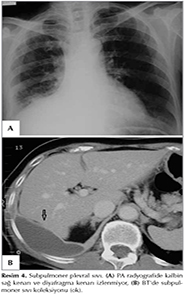

Kalsifiye Plevra Plakları

Plevrada lokalize plaklarda g?r?lmektedir. Sıklıkla asbest temasından 30-40 yıl sonra gelişmektedir. Kalsifikasyonlar g?ğ?s duvarı boyunca, diyafragma kubbesinde veya kalp konturu boyunca lokalize olmaktadır. Frontal pozisyonda (anfaz) d?zensiz kenarlı ?ınar ağacı yaprağına benzer (holly leaf) bulgu vermektedir (Resim 8). Oblik radyografiler parankimde lokalize nod?ler lezyonlardan ayırt edilmesinde yararlı olabilir (23). Plevral kalsifikasyon saptanan olgularda ayırıcı tanıda ampiyem, t?berk?loza bağlı plevra tutulumu ve travmatik hemotoraks d?ş?n?lmelidir (5).

Resim 8